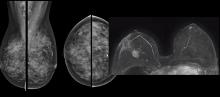

iCAD Inc. announced clearance by the U.S. Food and Drug Administration (FDA) for their latest, deep-learning, cancer detection software solution for digital breast tomosynthesis (DBT), ProFound AI. The solution built on artificial intelligence (AI) is now available to healthcare facilities in the U.S.

AI is also helping simplify complex tasks and help reduce the reading time on involved exams. One example of this is in 3-D breast tomosythesis with hundreds of images, which is rapidly replacing 2-D mammography, which only produces 4 images. Another example is automated image reconstruction algorithms to significantly reduce manual work. AI also is now being integrated directly into several vendors' imaging systems to speed workflow and improve image quality.